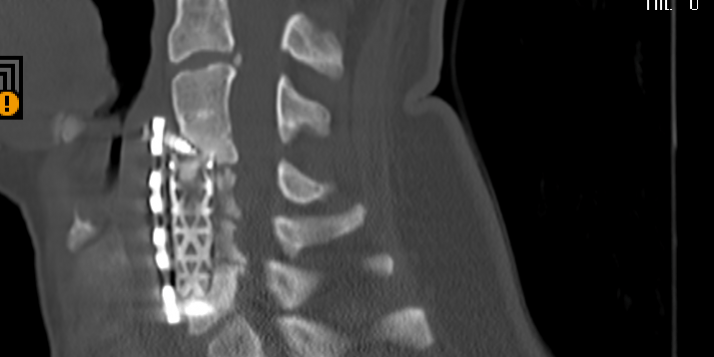

Ο απεικονιστικός έλεγχος με μαγνητική και αξονική τομογραφία της σπονδυλικής στήλης ανέδειξε εικόνα σωματεκτομής Α5, Α6 και μερικώς και Α7. Υπήρχε χαλάρωση των βιδών που καθήλωναν την πλάκα. Συνολικά εικόνα ψευδάρθρωσης και πίεσης επί του νωτιαίου μυελού και των αυχενικών ριζών (κυρίως Α7 δεξιά)

Διενεργήθηκε αρχικά οπίσθια σπονδυλοδεσία με διαυχενικές βίδες Α4, βίδες στα πλάγια ογκώματα Α5 και διαυχενικές βίδες Α7 και Θ1 ενώ έγινε και τρηματεκτομή Α6/7 δεξιά.

Στη συνέχεια, αφαίρεση της πρόσθιας πλάκας, ολοκλήρωση της σωματεκτομής Α5 & Α6, απελευθέρωση του νωτιαίου μυελου, πρόσθια δισκεκτομή Α7/Θ1 και τοποθέτηση πρόσθιας πλάκας Α4-Θ1.